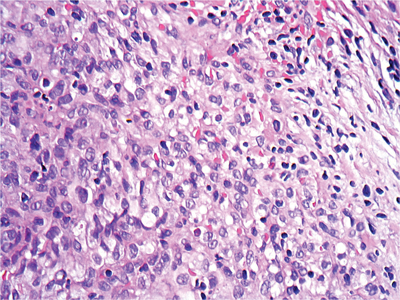

1. Describe Figure 1 (haematoxylin and eosin stain).

1. A spindle cell neoplasm, composed of uniform cells with minimal nuclear pleomorphism.

2. This figure shows a ‘sieve-like’ pattern of the spindle cells cut end on, with erythrocytes in-between.